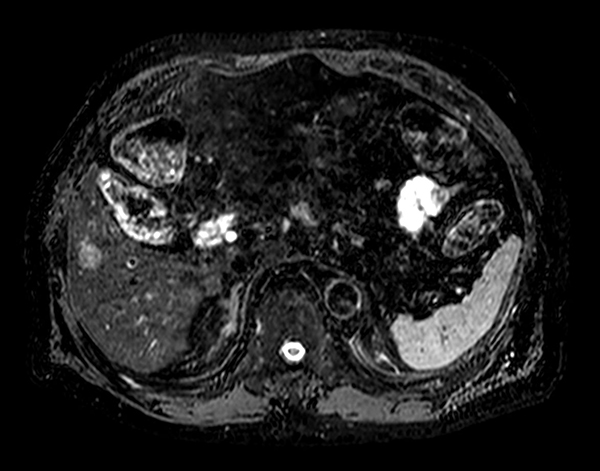

Axial mDIXON Quant